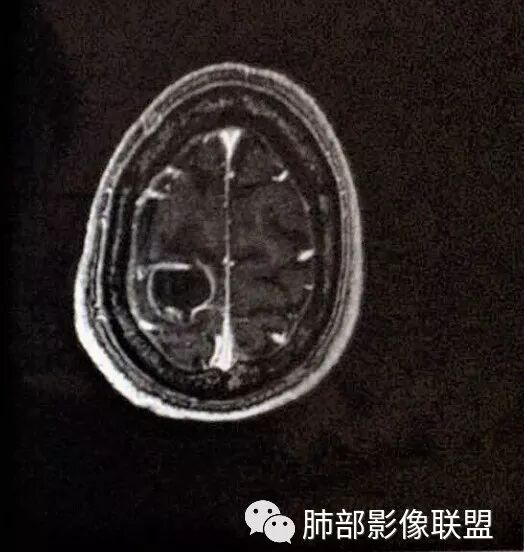

脑内多发结节,DWI壁弥散受限,腔不受限

强化内外壁部分区域稍毛糙

颅内环形的高信号,但是可以发现这个的DWI环是厚的,但是增强扫描的环是非常薄的,如果是肿瘤的,就是壁的弥散受限是肿瘤细胞的话,那么他强化的环应该跟DWI的环的厚度是一样的,所以这个环形的低DWI高信号应该是脓肿。而且就是关于这个脓腔壁的,就是脓腔的外壁是非常模糊的,而内壁还是相对光整,环不是很完整。下面一个图,没有给到,DWI上可以看到沿着破溃的脓肿壁向外侵出去的感觉,如果是环形转移的,那么它的那个内壁是更加不光整,而外壁是相对比较清楚一些的。

这个颅内病灶增强扫描的无强化区范围与DWI高信号范围是一致的,所以还是脓腔内受限,至少时期不那么典型,不是纯粹的高信号,DWI是厚层、增强是薄层;而且扫描角度也不一样,所以无法完全对上

脓肿内的坏死、脓液形成也不是一次性完全形成的,就像在肝脓肿内,信号也是不一致的。重点还是在于强化区的地方弥散受限了还是无强化区的地方受限了,还是那句话,强化壁比弥散壁薄很多,无强化区比弥散不受限区范围大多了

3.脑内多发混杂信号病灶,显著长T1、显著长T2信号为主。注意TW1及TW2均显示环形等密度影(这在转移瘤是非常罕见的)且出现相应的环形强化。中央液化区DW扩散受限以及周边广泛水肿等,都符合典型多发脑脓肿改变。